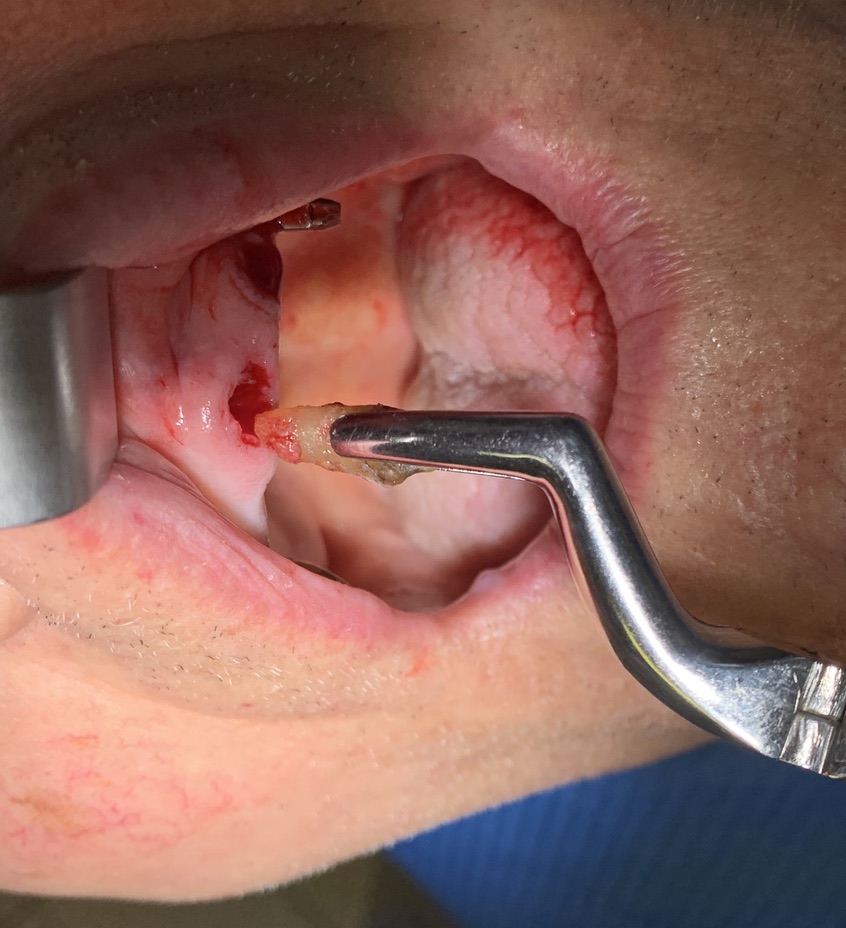

Tipo di impianto: Tramonte     Numero di impianti inseriti: 2     Saldatura: No    Zona dentale: 21   23

Operatore 1:  Dr. Bellini    Operatore 2: Dr. Bazzoli     Sequenza frese: Solo fresa lanceolata    Sequenza maschiatori: solo diametro 4 mm.

E- riducono il consumo di osso quasi a zero, per la perforazione e l’inserimento,

O- le manovre chirurgiche risultano così poco invasive e garbate da rendere gli impianti di Tramonte indicati in età avanzata, nei fumatori, nelle malattie croniche

V- anestesia solo puntata, minima,